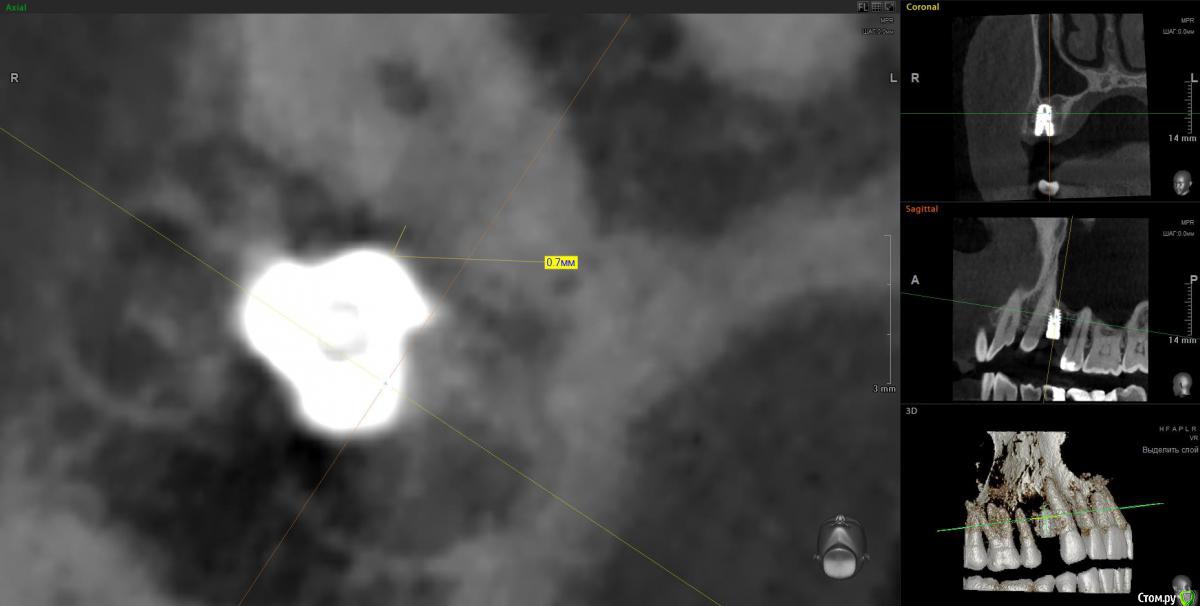

Doctor Vlad Опубликовано 14 апреля, 2020 Поделиться Опубликовано 14 апреля, 2020 Вчера одномоментно. кт только сегодня. Жалоб нет. Хотя там и сст с неба. конечно клык не сверленый, но близость напрягает. Съехал он при установке. Поленился снимок делать после установки, ушил лунку с трансплантатом, во рту норм выглядел. А потом на рг не очень) контроль кт Оставить? убрать недели через 3? Ссылка на комментарий

It'sGeorgy Опубликовано 14 апреля, 2020 Поделиться Опубликовано 14 апреля, 2020 Вчера одномоментно. кт только сегодня. Жалоб нет. Хотя там и сст с неба. конечно клык не сверленый, но близость напрягает. Съехал он при установке. Поленился снимок делать после установки, ушил лунку с трансплантатом, во рту норм выглядел. А потом на рг не очень) контроль кт Оставить? убрать недели через 3?Если есть уверенность, что в следующий раз получится поставить лучше и успешно провести ЗСЛ - я бы убрал. Какие показания к удалению? Я бы оставил, не вижу проблемы 0.7 мм рисково между зубов и винтом, на мой взгляд оставлять. Ну и по глубине тоже, ябдокрутил. Ссылка на комментарий

Doctor Vlad Опубликовано 14 апреля, 2020 Поделиться Опубликовано 14 апреля, 2020 Если есть уверенность, что в следующий раз получится поставить лучше и успешно провести ЗСЛ - я бы убрал. 0.7 мм рисково между зубов и винтом, на мой взгляд оставлять. Ну и по глубине тоже, ябдокрутил. было такое в практике, чем опасно? Ссылка на комментарий

Doctor Vlad Опубликовано 14 апреля, 2020 Поделиться Опубликовано 14 апреля, 2020 Имплант с полированной шейкой, по замерам мм на 2 ниже вестибулярной пластинки Ссылка на комментарий

Irouil Опубликовано 14 апреля, 2020 Поделиться Опубликовано 14 апреля, 2020 глубины мало?Платформа впритык к зубу, риск формирования кармана очень велик 1 Ссылка на комментарий

Doctor Vlad Опубликовано 16 апреля, 2020 Поделиться Опубликовано 16 апреля, 2020 Объясните-в чем опасность? Не понимаю...С зубом проблем не будет, имплант без компрессии там лежит и не травмирует. Но в плане протезирования и долгосрочной перспективы хочется видеть его ровней и на равном удалении от зубов. следующий имплант будет уже. ось его на центр выходит между 13 и 15 но 1 мм от платформы до 13 зуба маловато. Опыта в таких случаях нет. В нижних резцах тоже бывает меньше мм 1 остается и все норм. Хотелось бы поглубже. Сейчас он на мм 2 заглублен от кортикалки и мм 3.5 по десне. но пройдет ремоделировка и будет меньше, а может и нет. Если бы я его протезировал может быть оставил бы посмотреть. Ссылка на комментарий